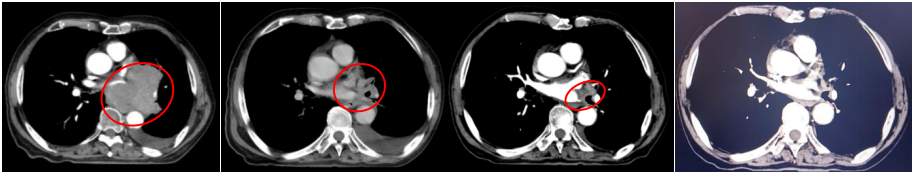

胸部增强CT(2022-05-23):1、左肺门占位(较大截面约7.8cm×8.3cm)伴纵隔多发肿大淋巴结、远端阻塞性肺炎、考虑中央型肺癌,累及左肺动脉及左心房、心室不除外。2、双肺肺气肿。3、左侧胸腔积液,累及左侧胸膜可能。4、心包少量积液。5、肝内多发小囊肿可能。

2022-07-19(2周期后)胸部、全腹部增强CT:1.肺癌复查,较前(2022-05-23)左肺门占位明显减小,左肺下叶远端阻塞性改变较前范围减小;2.双肺肺气肿;3.左侧胸腔积液,累及左侧胸膜可能,较前略增多;4.心包少量积液,较前增多;5.肝内多发囊肿;右肾上极小囊肿;6.肝左叶内小海绵状血管瘤可能;7.前列腺增大伴钙化。